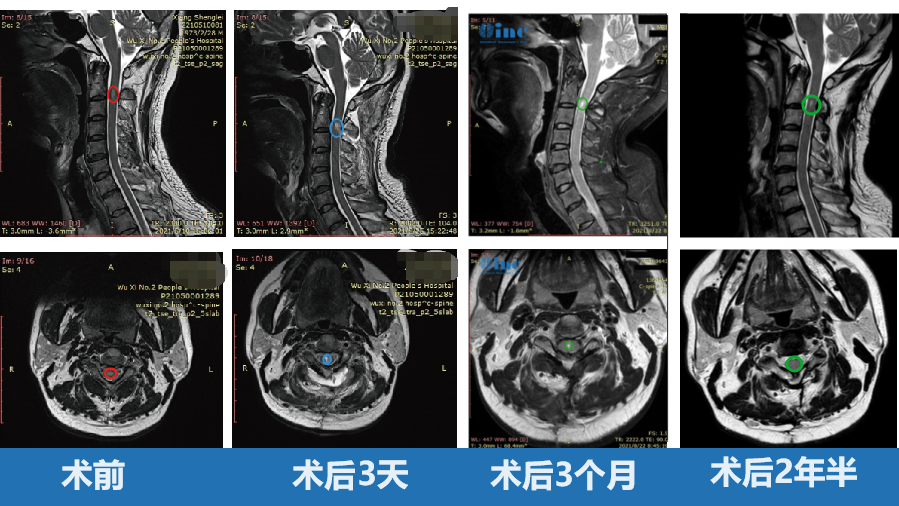

术前颈 2 平面脊髓内可见椭圆形短 T1 长 T2 信号,信号较均匀,边界尚清,大小约 7. 8X4.1X5.0mm,增强后明显强化。术后肿瘤得到顺利全切,无新发神经损伤,无瘫痪,术后复查未复发。